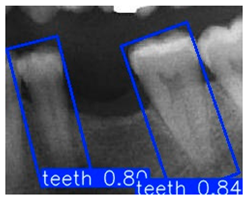

| YOLO-OBB result | ||||||

| Validation Image 1–6 | ![]() | ![]() | ![]() | ![]() | ![]() | ![]() |

| Accuracy | 84.13% 75.18% | 90.29% 76.49% | 87.38% 87.27% | 80.40% 84.48% | 70.11% 83.41% | 88.46% 76.33% |